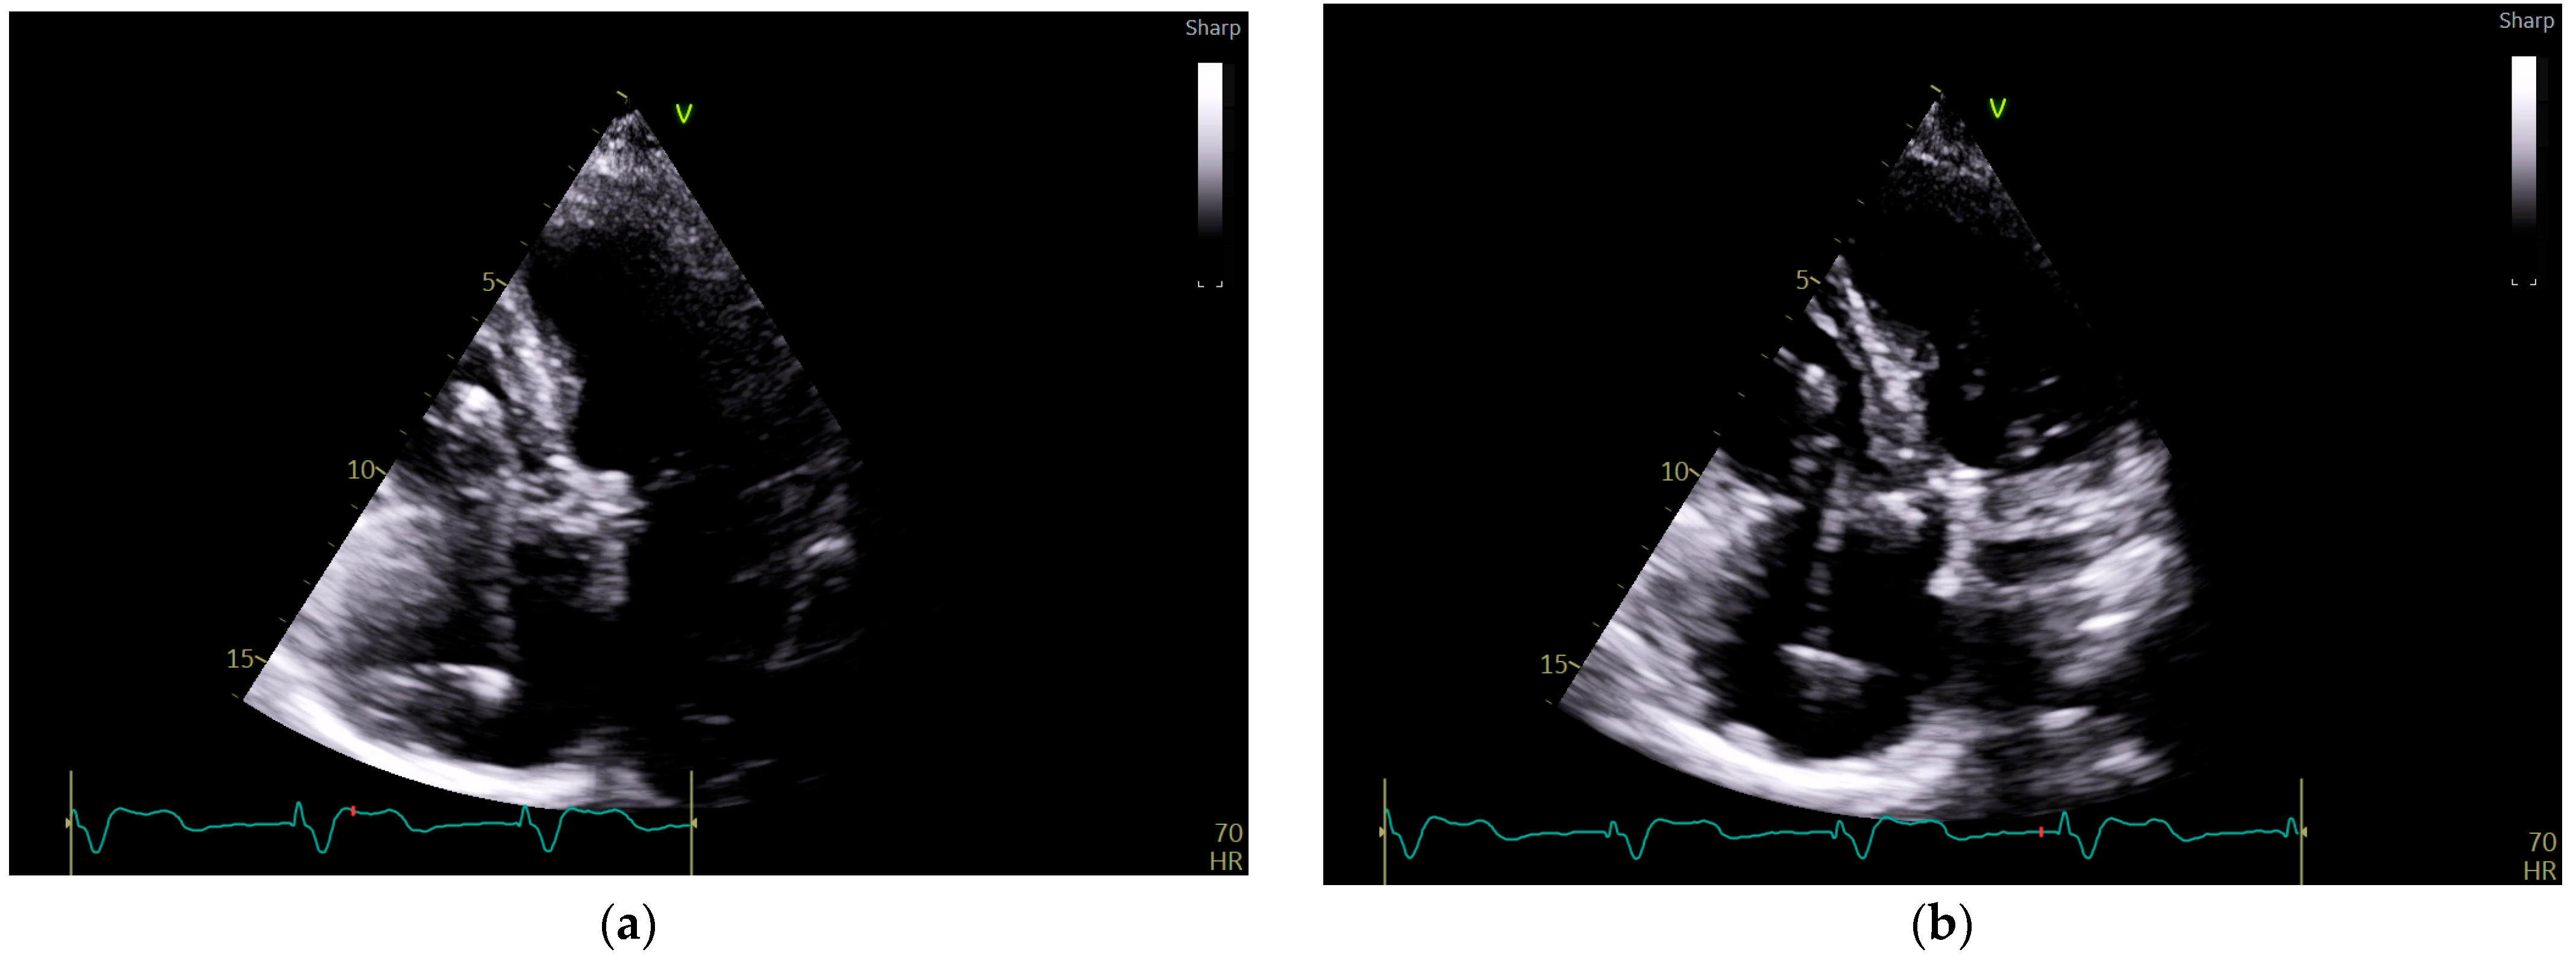

To investigate a potential cause of malfunction of the intracardiac device, it was decided that both a chest X-ray (Figure 2) and an echocardiogram (Figure 3) would be performed. These diagnostic tests were selected to confirm or rule out the possibility of a pacing probe fracture, particularly considering the patient’s recent fall, which may have compromised the integrity of the device or the intracardiac pacing leads. The chest X-ray assesses the device positioning and identifies potential fractures of the pacing leads. Concurrently, the echocardiogram provides critical information regarding cardiac function and its interaction with the implanted device. Together, these diagnostic modalities are essential for optimal management of the patient.

Figure 2. Patient chest X-ray at admission: a cardiac pacemaker is present in the right pectoral region with a ventricular stimulation lead placed on the free wall of the right ventricle and an abandoned atrial lead. There is no apparent lead displacement or fracture. The inferior segment of the left border of the heart is elongated and bulging. An aortic prosthetic valve is present. There are no pleural or pulmonary lesions.

In the event of a suspected malfunction of a pacemaker in a stable patient, the initial assessment should start with a surface ECG and a chest radiography, which are essential in evaluating the pacemaker’s hardware and function. Chest radiography is effective in identifying lead displacement and gross lead fracture, although the latter is uncommon with modern devices. Chest X-ray alone has 71% sensitivity and 100% specificity in diagnosing lead fracture [13].

In the elderly population, myocardial perforation by the pacing lead has an incidence of 2.2% [14]. Chest radiography has a sensitivity of 27.7% and a specificity of 94.4% in identifying this complication. The addition of echocardiography is valuable in this setting, as it has an increased diagnostic sensitivity of 41.2%, while the specificity is 84.2% [15]. However, chest radiography is limited in its ability to detect subtle abnormalities, such as lead insulation defects or microdisplacement of the pacing electrode [16].